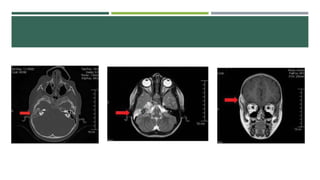

TROMBOSIS DEL SENO SIGMOIDEO

 Asintomatico. Parestesias, fiebre, datos de

toxemia, torticolis, embolizacion séptica.

 Alteraciones en el habla, coma, muerte.

 Factores sistémicos (LDL, Ac Beta 2

glicoproteína, Cardiolipina)

 TC, RM.

 Mastoidectomia, retiro de tejido de granualcion

extradural

 Anticoagulantes, antibióticos.

TROMBOSIS DEL SENOSIGMOIDEO  Asintomatico. Parestesias, fiebre, datos de toxemia, torticolis, embolizacion séptica.  Alteraciones en el habla, coma, muerte.  Factores sistémicos (LDL, Ac Beta 2 glicoproteína, Cardiolipina)  TC, RM.  Mastoidectomia, retiro de tejido de granualcion extradural  Anticoagulantes, antibióticos.